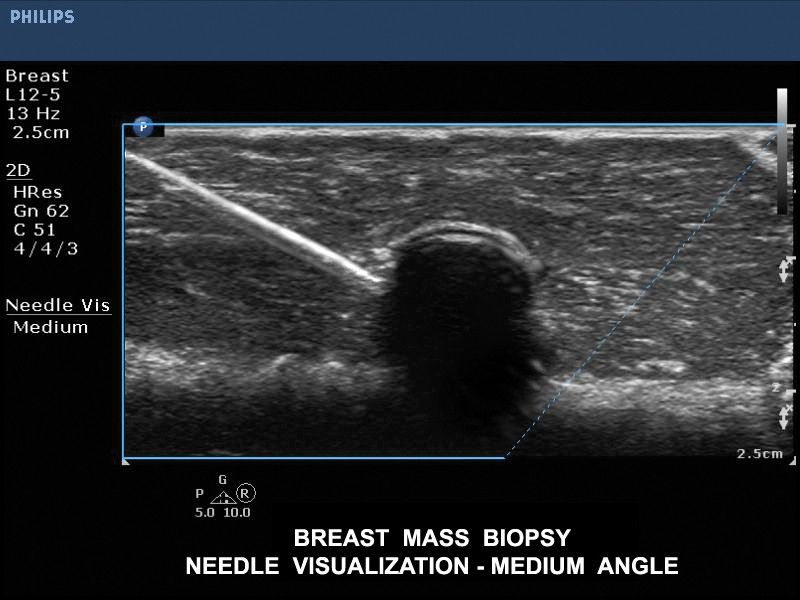

Визуализация иглы при биопсии молочной железы, датчик L12-5